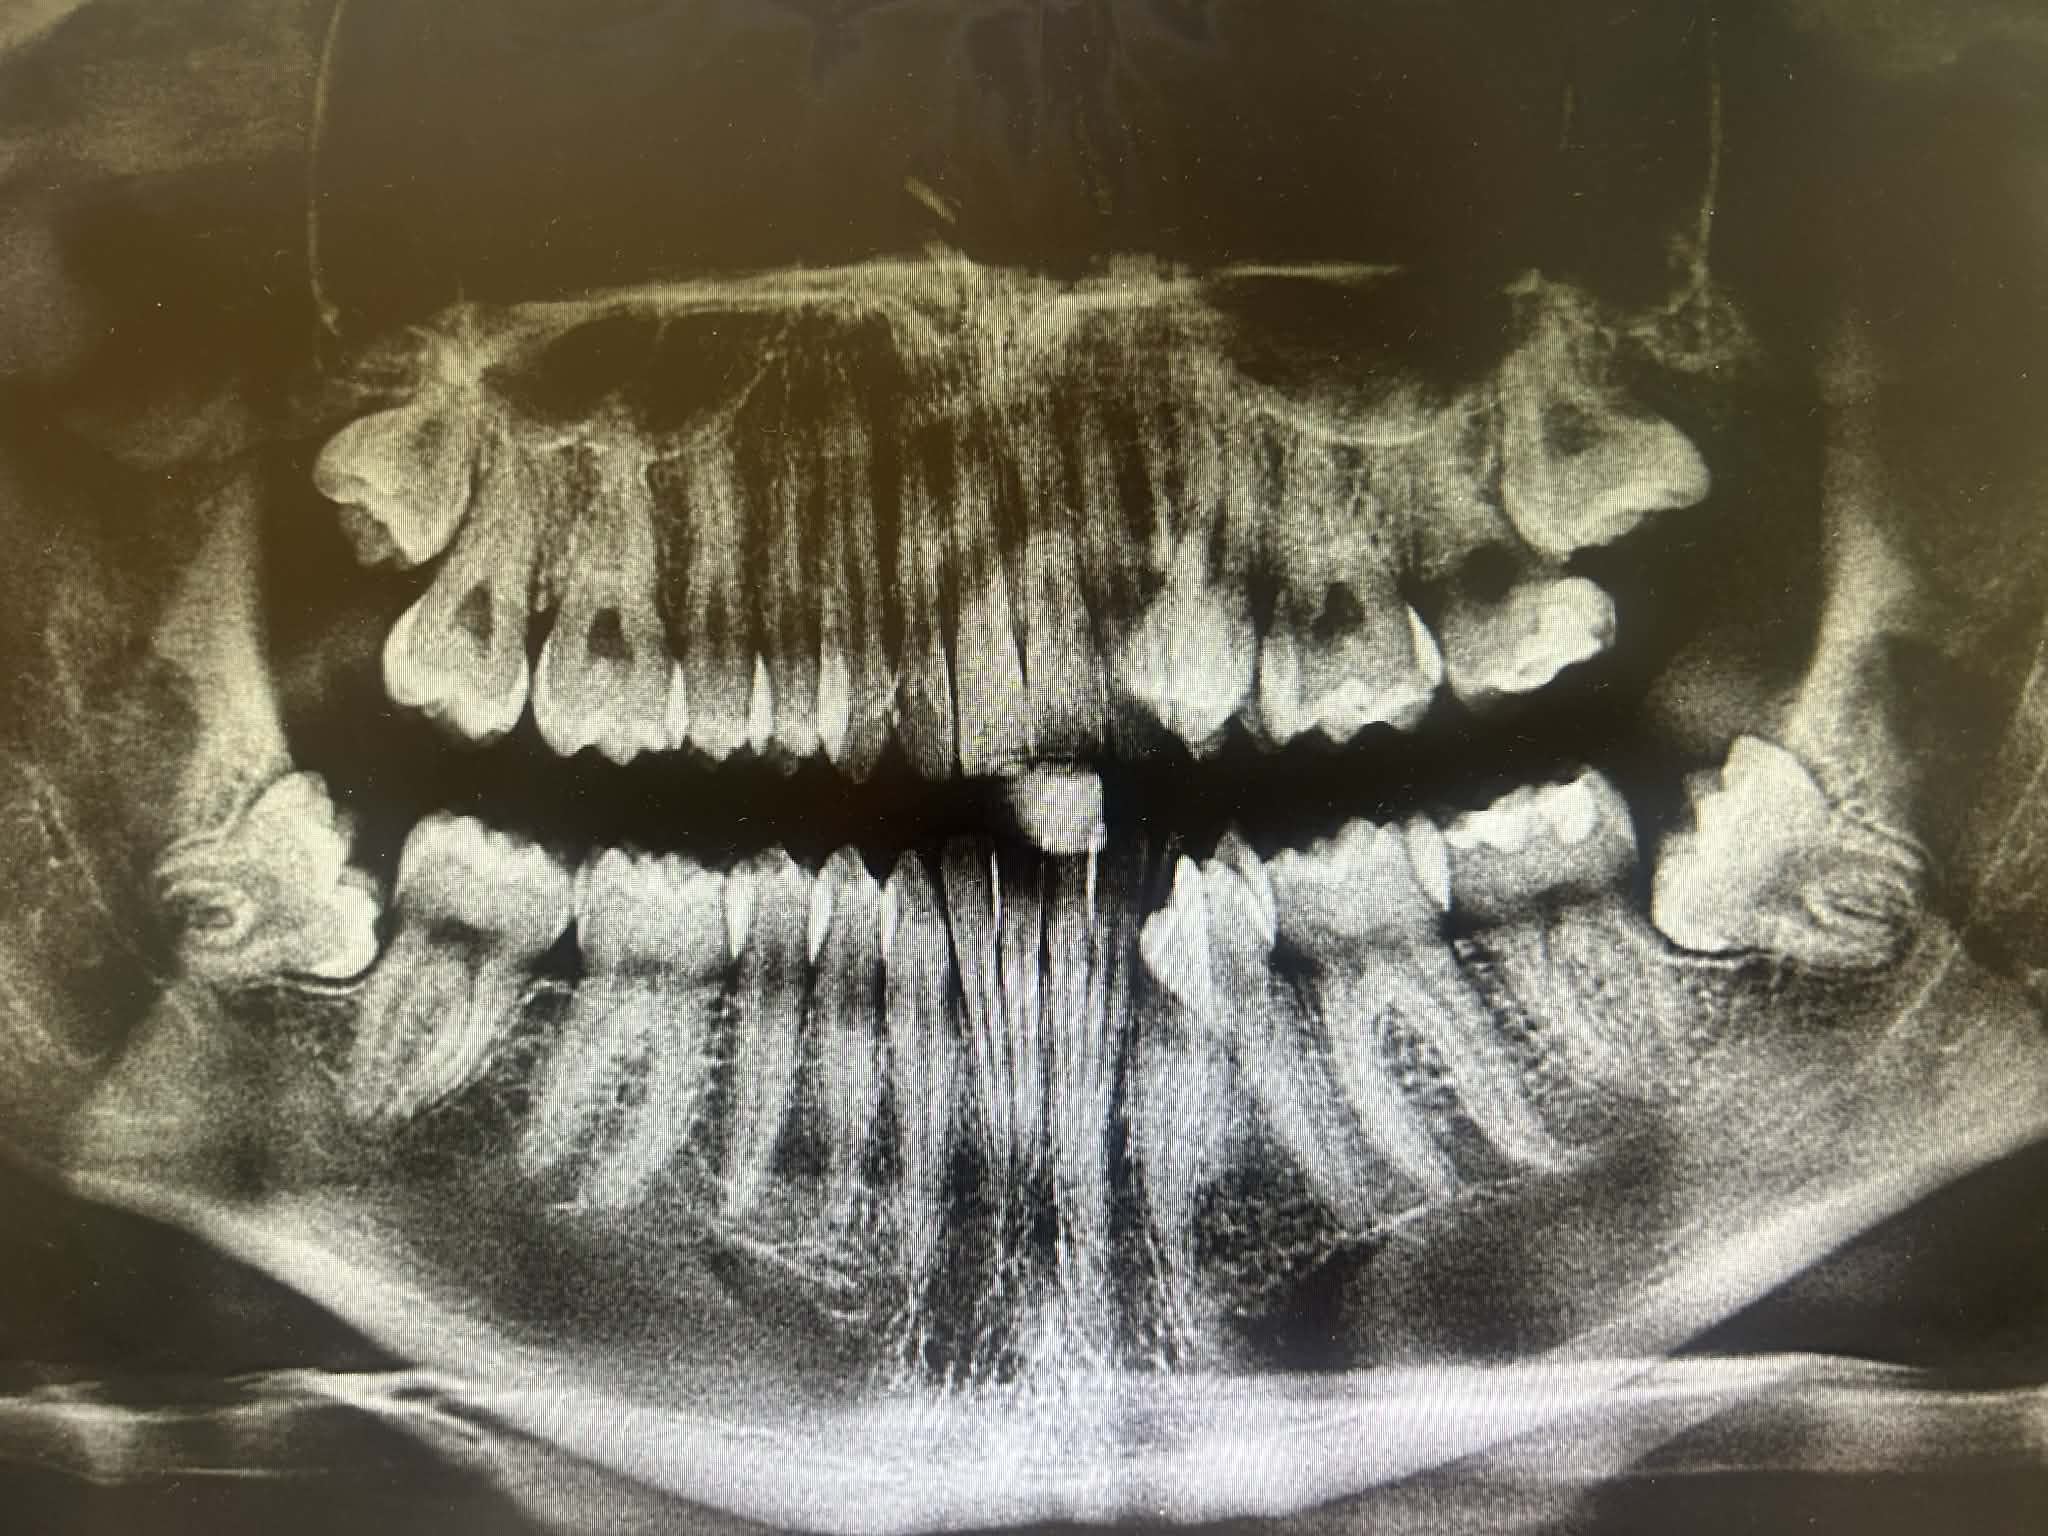

Cooked fuck bro this is worse then my crowdingwondering if my palate is better, went to the orthodontist but instead of giving me a CBCT they just took pictures with a Polaroid camera but atleast their more clear.

How narrow does my palate look to youGeomaxx to Germany

Its kinda bad tbh also You have a slight underbite , you can still fix it tho Brother I wish I Best KickHow narrow does my palate look to you

I’ve suspected a skeletal Class III but what makes you say I have an underbite just judged from the photos because my upper jaw isnt more retracted then the lower one atleast in terms of alveolar structureIts kinda bad tbh also You have a slight underbite , you can still fix it tho Brother I wish I Best Kick

Yeah your maxilla is definetly narrow and recessed. I know how you told me how they won't give it to you but marpe and face mask is your only bet rn. adn they need to do it quickly.You’d say my maxilla is both recessed and narrow. Anyways yes these orthos just want to money, they’re so money hungry that they can’t even realise their job is to help those with issues not make them worse. How do you think I should move from here to fix this problem? Is MSE + face mask enough